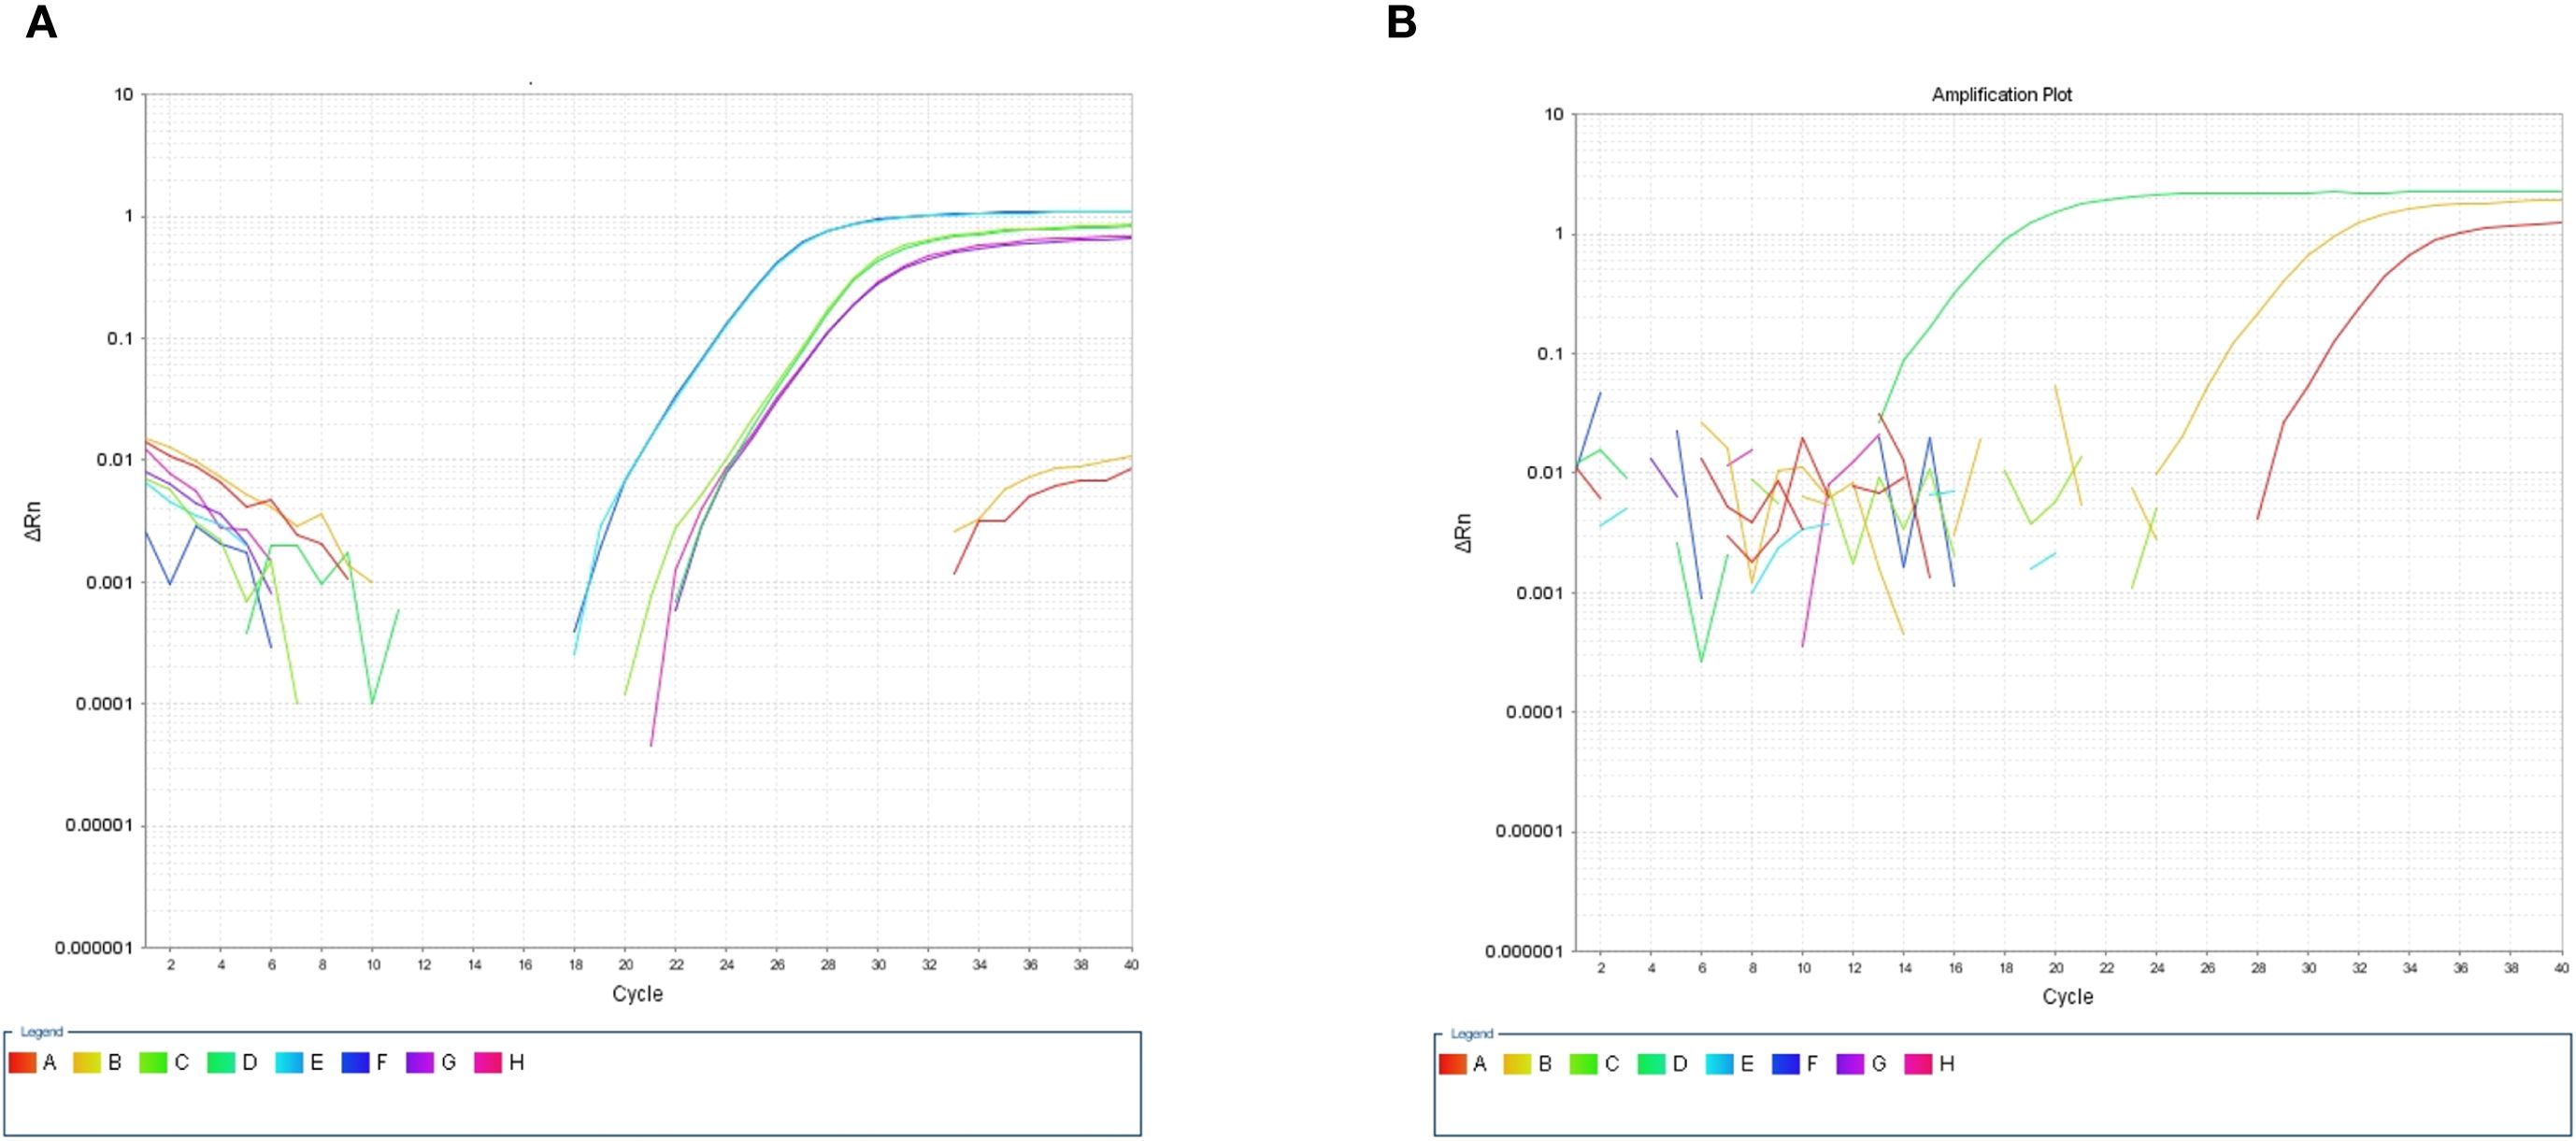

After the patient’s hospital admission, his chest X-ray revealed bilateral pneumonia and ground-glass opacity, and he was prescribed oxygen therapy and doxycycline. Afterward, lesions with ground-glass opacity were reduced, but pulmonary consolidation was still observed in the lungs (Supplementary Figure S2). Based on 23S rDNA amplification, a positive 172-bp band of C. psittaci was detected in the patient’s alveolar wash, while his tracheal mucosa and throat swabs were negative (Figure 1A). Other family members, the nurses, the attending physician, and the house chickens were negative for C. psittaci (Figure 1B). Afterward, qPCR results showed that the patient’s alveolar wash was positive for C. psittaci. Subsequently, positive C. psittaci was identified in the patient’s alveolar wash and throat swab, and his sons’ throat swab. However, a negative reaction was found in his tracheal mucosa and other close contacts’ samples (Figure 2). The ompA gene sequence of the C. psittaci strain was determined and submitted to GenBank (accession number: OR616243). After inoculation into SPF embryonated eggs, typical intracellular inclusions were observed using immunofluorescence staining (Figure 3).

Figure 2. Detection of Chlamydia psittaci using qPCR assay. (A) Positive C. psittaci was detected in patient’s alveolar lavage and throat swab, while negative reaction was detected in tracheal mucosa. A, B: Tracheal mucosa, C, D: throat swabs, E, F: alveolar lavage, and G, H: C. psittaci. (B) Positive reaction was identified in his son’s throat swabs (D), and negative reaction was identified in his close contact’s samples: tracheal mucosa (A–C, E–H).